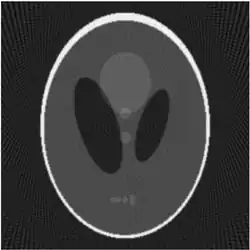

If a function represents an unknown density, then the Radon transform represents the projection data obtained as the output of a tomographic scan. The inverse of the Radon transform can be used to reconstruct the original density from the projection data, and thus it forms the mathematical underpinning for tomographic reconstruction, also known as iterative reconstruction.

The process of reconstruction produces the image (or function in the previous section) from its projection data. Reconstruction is an inverse problem.

Compared with the Filtered Back-projection method, iterative reconstruction costs large computation time, limiting its practical use. However, due to the ill-posedness of Radon Inversion, the Filtered Back-projection method may be infeasible in the presence of discontinuity or noise. Iterative reconstruction methods (e.g. iterative Sparse Asymptotic Minimum Variance[10]) could provide metal artefact reduction, noise and dose reduction for the reconstructed result that attract much research interest around the world.

Explicit and computationally efficient inversion formulas for the Radon transform and its dual are available. The Radon transform in dimensions can be inverted by the formula:[11] where , and the power of the Laplacian is defined as a pseudo-differential operator if necessary by the Fourier transform: For computational purposes, the power of the Laplacian is commuted with the dual transform to give:[12] where is the Hilbert transform with respect to the s variable. In two dimensions, the operator appears in image processing as a ramp filter.[13] One can prove directly from the Fourier slice theorem and change of variables for integration that for a compactly supported continuous function of two variables: Thus in an image processing context the original image can be recovered from the 'sinogram' data by applying a ramp filter (in the variable) and then back-projecting. As the filtering step can be performed efficiently (for example using digital signal processing techniques) and the back projection step is simply an accumulation of values in the pixels of the image, this results in a highly efficient, and hence widely used, algorithm.